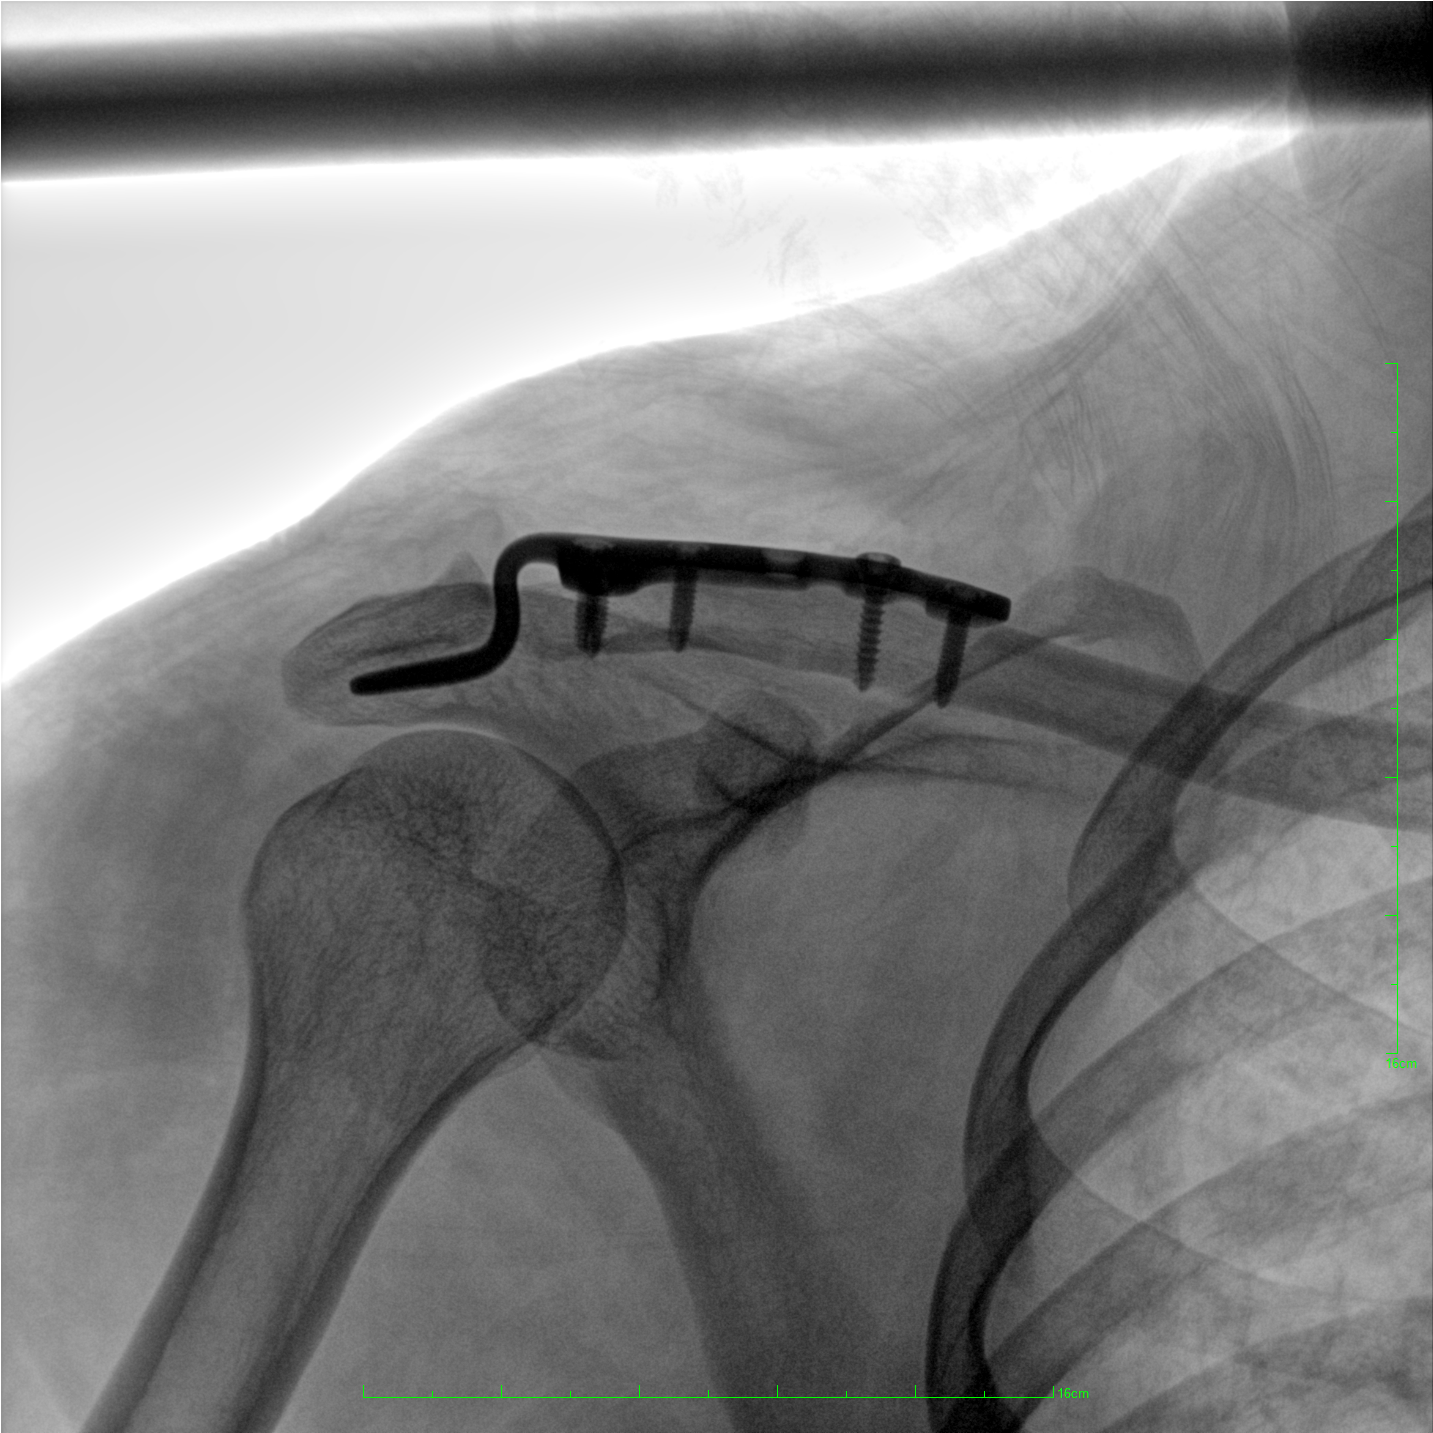

成像清晰、操作簡(jiǎn)易、擺位便捷,主要適用于骨科、脊柱外科、矯形外科、創(chuàng)傷骨科及手術(shù)室等,能大幅度提升手術(shù)水準(zhǔn),降低手術(shù)風(fēng)險(xiǎn)和并發(fā)癥的概率。

術(shù)中三維成像和橫斷面圖像提供多角度的手術(shù)診斷信息,輔助醫(yī)生進(jìn)行術(shù)中評(píng)估判斷,諸如骨折復(fù)位情況和內(nèi)植入螺釘?shù)某叽绾臀恢?,輔助手術(shù)更好地完成。